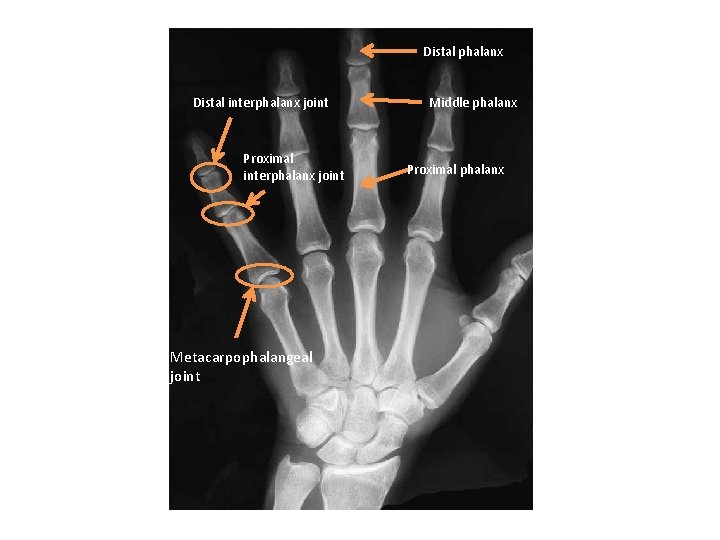

HAND

X RAY

Distal phalanx Distal interphalanx joint Proximal interphalanx joint Metacarpophalangeal joint Middle phalanx Proximal phalanx